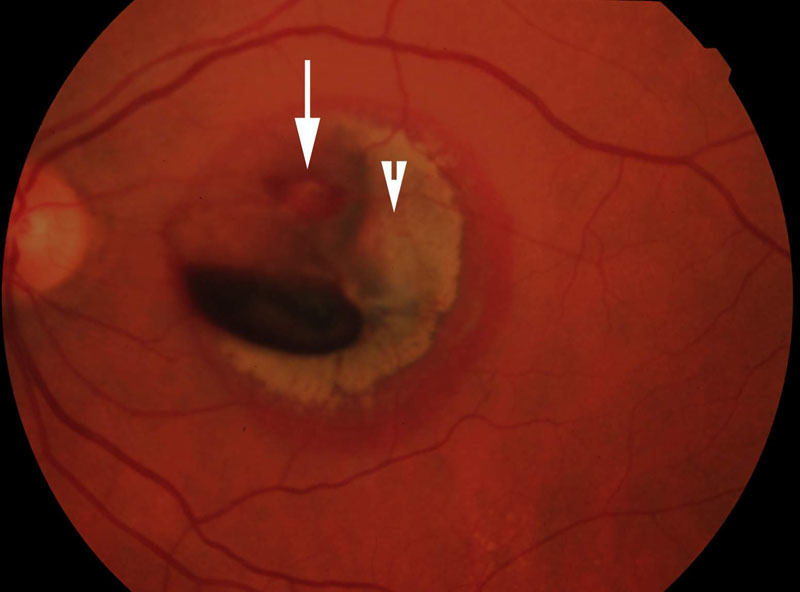

1. ábra

1. ábra Óriás szakadás következtében kialakult ablatio retinae szemfenéki képe. A QuadrAsphericus lencse széle látószögének köszönhetően gyorsan áttekinthetjük a fundus egészét. Jól érzékelhető az óriás szakadás kötényszerűen előrehajló hátsó széle.

36. ábra

36. ábra Artériális macroaneurisma következtében a maculatájon prae- és subretinális vérzéseket alakultak ki. A funduskamerával készített felvételen a nyíl a macroaneurismára mutat, a nyílhegy a hátsó üvegtesti kéreg praemacularis foramenjét jelzi. A foramen körül az üvegtesti kéreg gyűrűszerűen megvastagodott. A biomikroszkópos vizsgálat a gyűrű temporális felének elemelkedésével járó részleges hátsó üvegtesti leválást talált. Feltételezhető, hogy a macroaneurisma rupturáját a kóros vitreoretinális adhaesio provokálta.